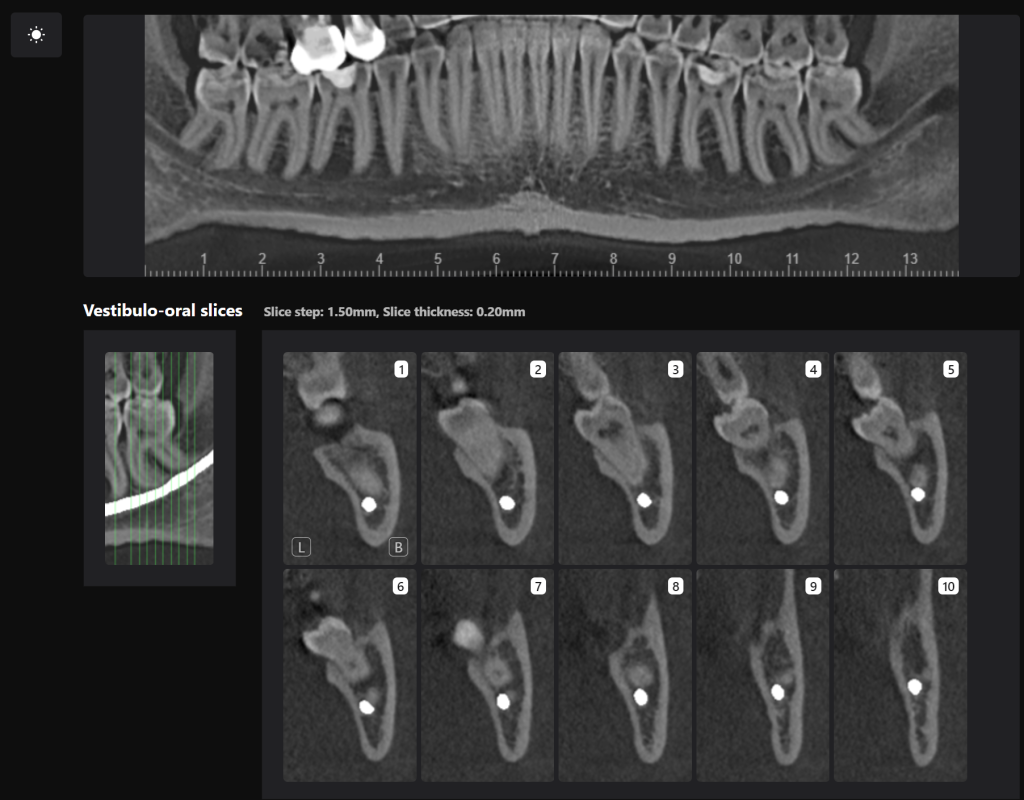

“Third Molar Report” created by Diagnocat AI, is a tool which provides accurate tracing of the mandibular canal

And creating an optimal 3D visualization which helps the clinician to determine the distance to the mandibular canal

Teeth 38 (Universal 17) and 48 (Universal 32) were extracted with minimal surgical trauma and without causing damage to the inferior alveolar nerve